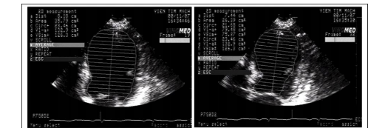

5.2.5. Đánh giá chức năng thất trái trên siêu âm 2D

- Đánh giá vận động vùng thành tim: Thực hiện trên 4 mặt cắt: trục dọc cạnh ức trái, trục ngắn cạnh ức trái, bốn buồng tim từ mỏm, hai buồng tim từ mỏm. Áp dụng cách tính điểm vận động vùng thành tim theo Hội Siêu âm tim Hoa Kỳ.

- Đo phân số tổng máu thất trái bằng phương pháp Simpson.

Hình 9. Đo phân số tổng máu thất trái bằng phương pháp Simpson.